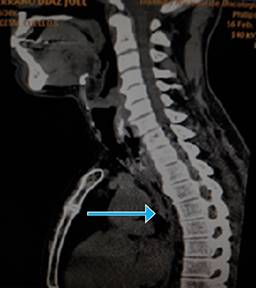

En la tomografía axial computarizada con contraste, en el cuello con cortes de 2 y 5 mm, se observó una imagen de alta densidad de 56 UH, alargada, que medía 17 mm de longitud entre el esófago cervical y el cartílago cricoides sugestivo de cuerpo extraño. Por encima de la misma, se detectó el esófago con paredes muy engrosadas de forma circunferencial que medía 20 mm, con longitud aproximada de 30 mm, provocando estenosis del mismo y compresión de la tráquea, engrosamiento de tejidos blandos con imagen blástica a nivel de T1 y T2 adyacente a la lesión descrita, adenopatía de 8 mm pretraqueal, cambios osteodegenerativos a nivel cervical (Figura 2).